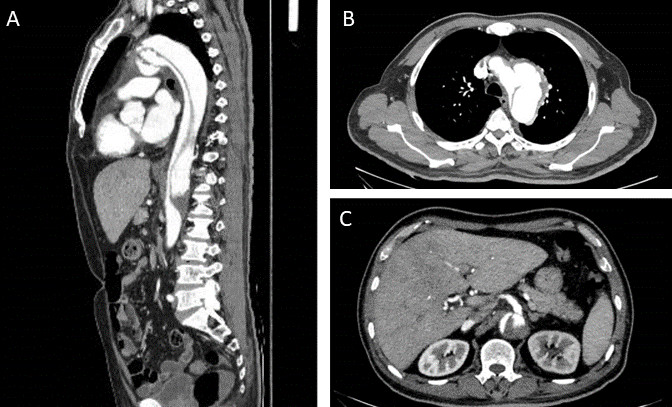

监测患者血流动力学稳定,临床评估提示NTS菌血症伴发B型主动脉夹层,鉴于菌血症,予以抗感染治疗(头孢曲松),计划感染控制后行手术干预。入院4 d后复查CT显示主动脉夹层向远处延伸,从主动脉弓延伸至腹主动脉中段,与L2-L3椎体水平一致;且真腔小于假腔,腹腔干和左肾动脉均起源于假腔(图 2),考虑假腔内高压挤压真腔。在充分抗菌和降糖治疗后,患者的感染指标逐渐下降,临床症状改善,遂建议进行手术治疗。但患者家属因经济原因放弃治疗,自行要求出院。出院1月余,患者于家中心搏骤停。

| A为Stanford B型主动脉夹层,夹层由主动脉弓延伸至腹主动脉中段L2-L3椎体水平;B为假腔大于真腔;C为腹腔干和左肾动脉均起源于假腔 图 2 起病23 d时胸腹盆增强CT |